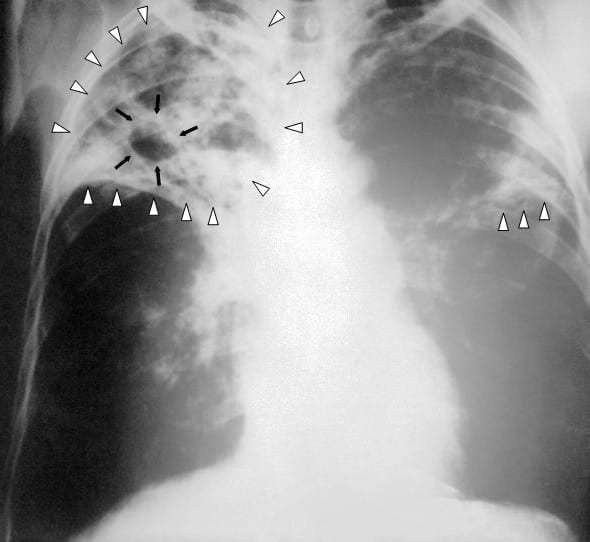

Nove compagni di classe sono risultati positivi al test Mantoux, confermati dal test di secondo livello. Esito negativo, invece, per gli stessi pazienti dall’esame radiografico del torace. Nelle altre classi controllate sono stati evidenziati tre soggetti positivi, nessuno confermato dal test di secondo livello e tutti con rx del torace negativo. Due studenti colpiti risultano essere vaccinati con vaccino antitubercolare BCG, con immunizzazione da micobatteri tubercolari non umani. Dal 15 febbraio si terranno i secondi screening sui soggetti esaminati e risultati negativi per finire il percorso di sorveglianza.